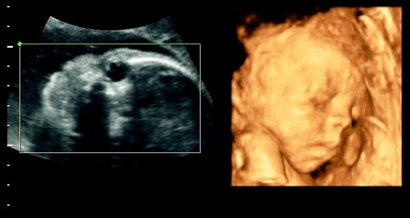

四维彩超是实时的立体成像,在孕检的时候主要是帮助筛查胎儿的畸形,四维由于清晰度高也有用来判断胎儿男女,那么四维看是男孩有可能是女孩吗,四维男翻女的几率多大?更多生男生女的相关内容尽在孕宝网。

四维彩超其实是实时的三维,是有一个立体成像的过程,因为胎儿是团抱式的,胎儿一部分会被遮挡,所以四维应该会更准确一些,但是不是绝对的。实际在B超进行胎儿性别鉴定时,有可能男孩生殖器被遮挡导致误认为是女孩,也可能把女孩的脐带当成生殖器误认为男孩,当医生正在操作B超的时分,若宝宝正处于背部的姿态或手脚正好蜷到一同,从而遮挡了性别器官,这也会形成性别的改动,另外假如你家宝宝太调皮了,不太配合,姿态不对,医生也不可以很精确的看到Ta的生殖器,结果就没有那么精确了,因此四维彩超虽然是比较精确的,但是也会出现错误的情况。

四:通过四维彩超图看清胎儿性别,在六个月以后照四维彩超,只要宝宝的姿势是正面不是给个背影什么的,是男是女一看就知道。不过因为国家明文规定不能查胎儿性别,所以医生不会把能明显看出性别的一面照给妈妈看。